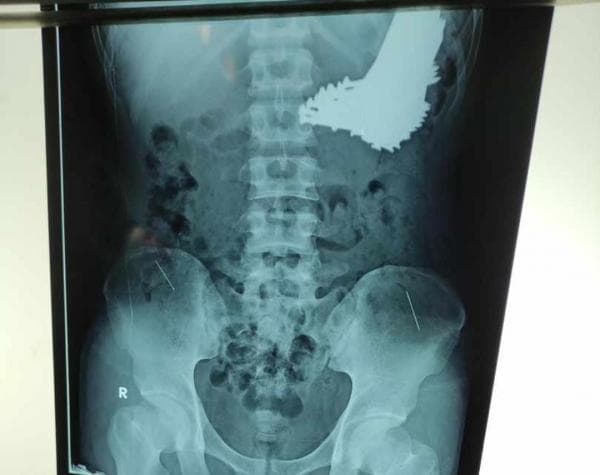

Kabar diketahuinya ada paku di dalam tubuh warga berjenis kelamin laki-laki itu setelah dirinya menjalani proses rontgen. Dari hasil foto rontgen tersebut diketahui ada banyak paku berukuran besar bersarang di dalam lambungnya.

Hasil dari tindakan operasi, dokter bedah RSUD Indramayu tersebut berhasil mengeluarkan sebanyak 70 batang paku dari lambung pasien. Sehingga pasien berhasil diselamatkan oleh tim medis.